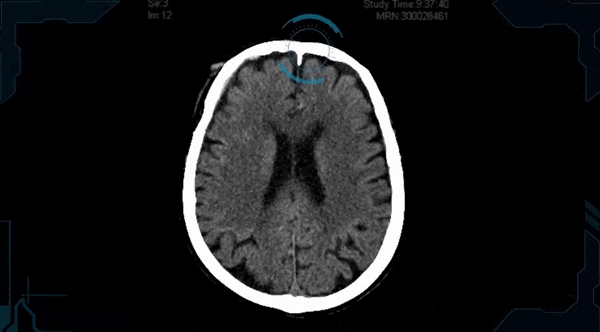

Offering a solution aimed at radiologists — and already deployed commercially across 100 sites — Aidoc claims to be able to detect high-level visual abnormalities from various types of medical scans. The idea is that by working in tandem with humans, it’s able to flag the most critical and urgent cases where a faster diagnosis and treatment could save lives.

Initially providing support for CT scans, the Israeli startup recently reached its millionth analysed patient scan. It says it is adding support for oncology and X-ray. The oncology solution will automatically and instantly detect, measure and compare tumour size with past scans as soon as the radiologist opens the image. I’m also told that another feature on the upcoming roadmap is support for MRI scans.